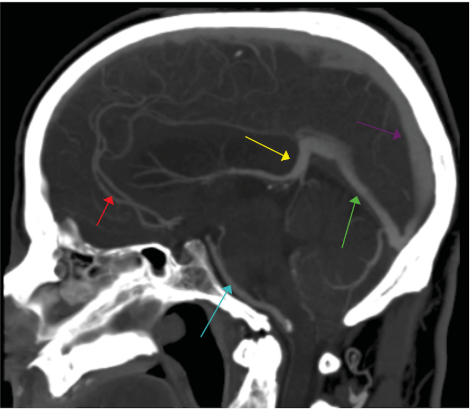

On the following CT angiogram, what does the purple arrow point towards?

Answer:

Superior Sagittal Sinus